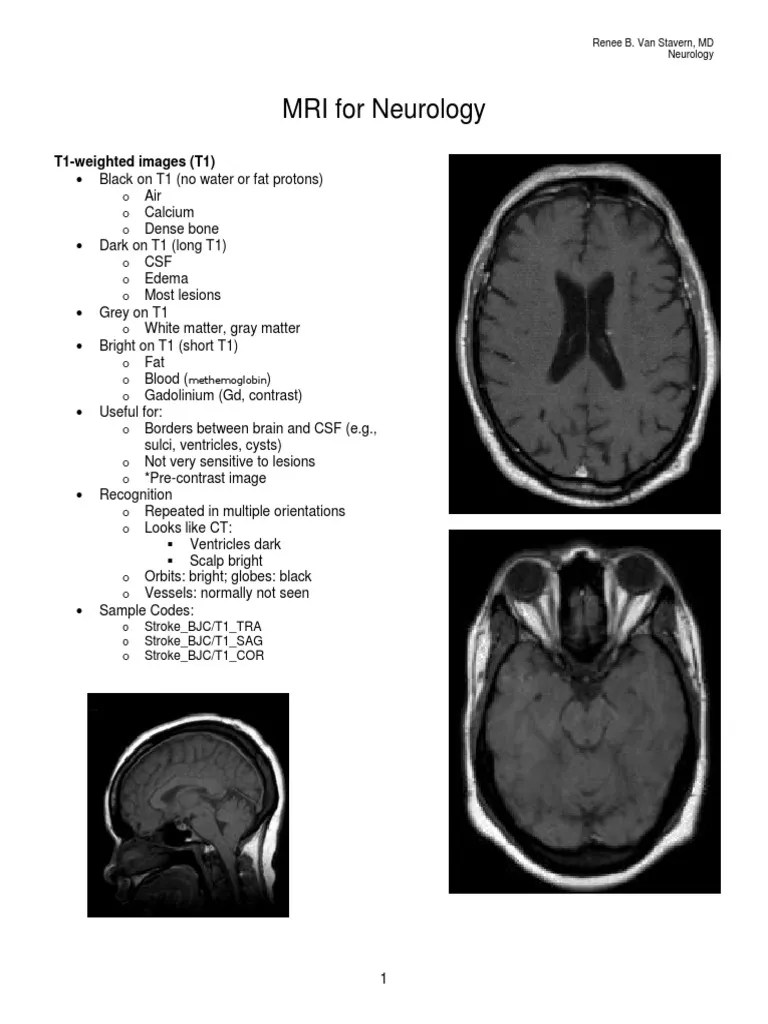

Week 3 Handout MRI for Neurology Resonance Imaging